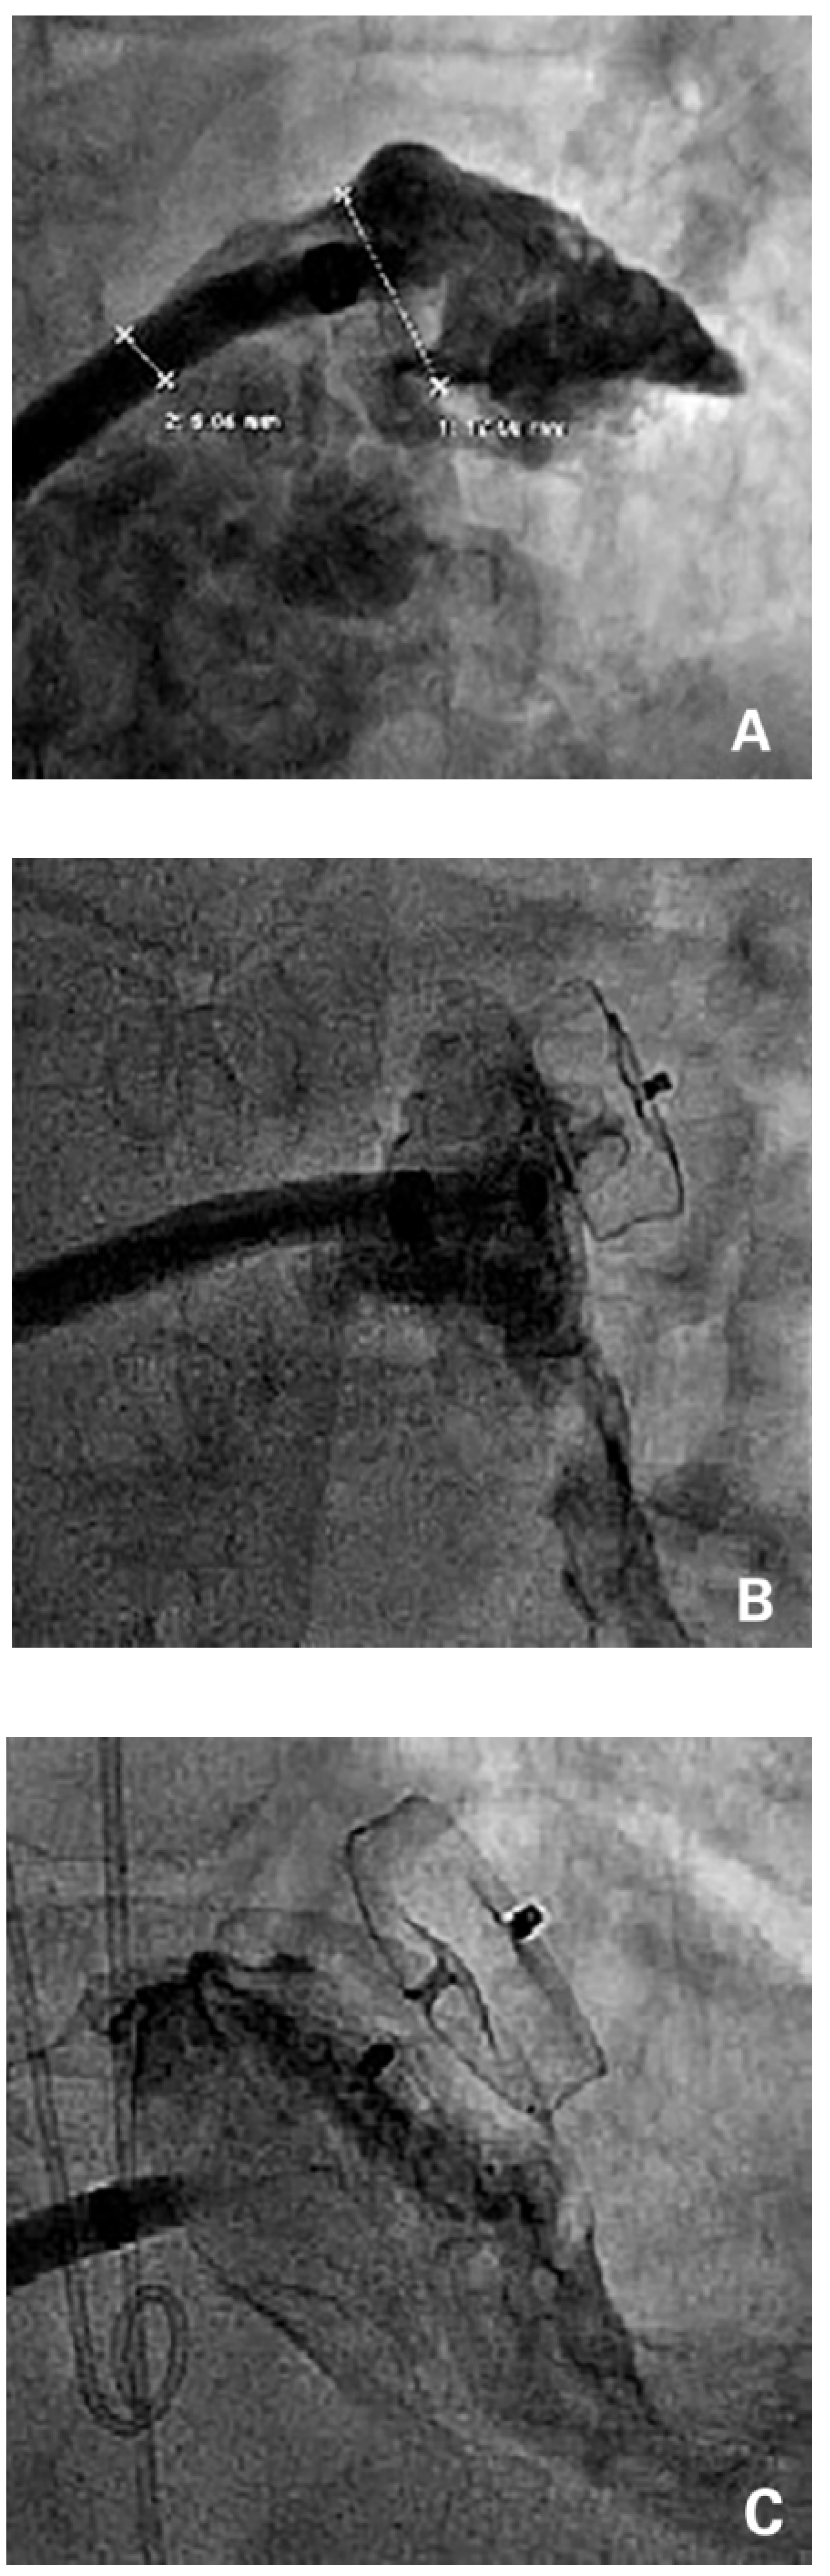

The landing zone, as well as the orifice and the length of the LAA were visualised and the size was estimated with use of contrast injections through the sheath in two angles (typically right anterior oblique [RAO] caudal and RAO cranial). If available, TEE or ICE was used for sizing. An at least 20% oversized device was selected accordingly or a device that best fitted the individual anatomy was used. After deployment of the device, a tug test and contrast injections were performed to confirm a stable device position [14] (Figure 2). Transthoracic echocardiography (TTE) was performed on the day of the procedure or the next morning to confirm a correct device position in the LAA. Patients were discharged on acetylsalicylic acid (ASA) 100 mg and clopidogrel 75 mg for 1–6 months. Oral anticoagulation was permanently stopped the day of the procedure.

Figure 2.

Device deployment. (A) Contrast injection to the left atrial appendage through a 14 French TorqVue 45×45 sheath with an outer diameter of 5.4 mm (left metering). Estimated diameter of the landing zone (right metering). (B) Amplatzer Amulet device still attached to the delivery cable. (C) Once a stable position was confirmed, the device was released.